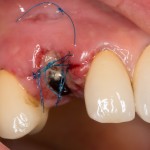

Итак, накладывается Mucograft Seal. Также успешно можно использовать любую коллагеновую матрицу любого размера:

Он подшивается узловыми швами. Операция закончена. Вид послеоперационной раны:

или вот:

У меня не было полной уверенности в том, что всё пойдет нормально, поэтому мы решили повременить с установкой коронки на имплантат до полного заживления раны, а это, примерно, несколько недель. Пациентка не против.